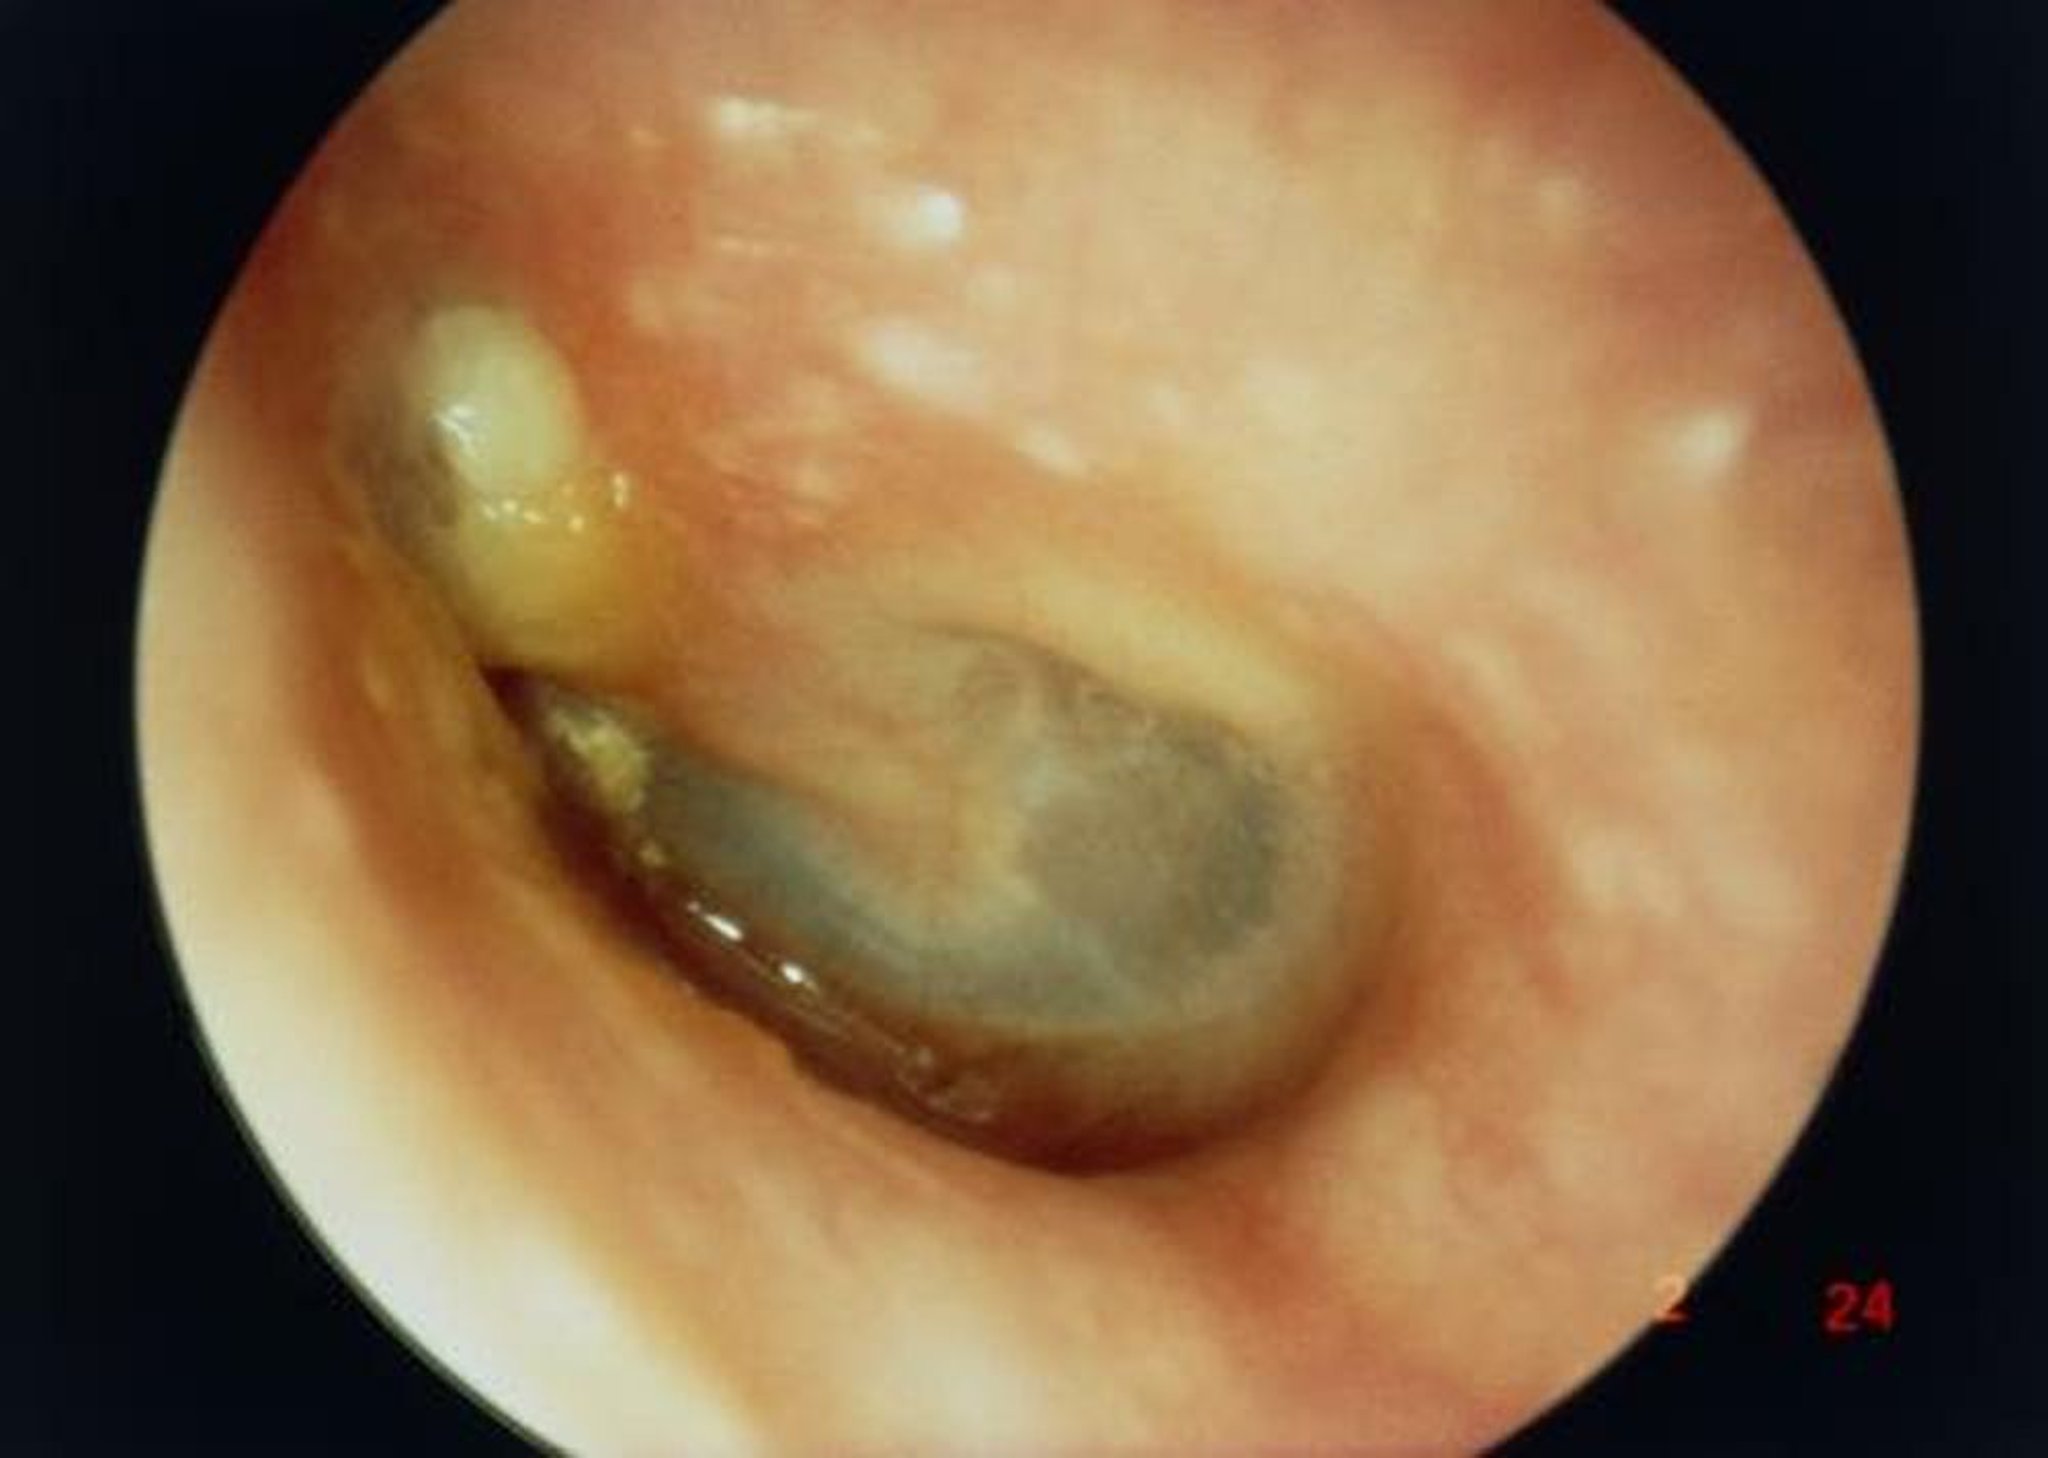

Cholesteatoma

Trong hình ảnh này, nhìn dọc theo ống tai ngoài cho thấy một khối cholesteatoma lớn (khối màu trắng ở bên trái phía trên mỏm xương búa ngắn), dẫn đến thủng màng nhĩ.

GIÁO SƯ TONY WRIGHT, INSTITUTE OF LARYNGOLOGY & OTOLOGY/SCIENCE PHOTO LIBRARY